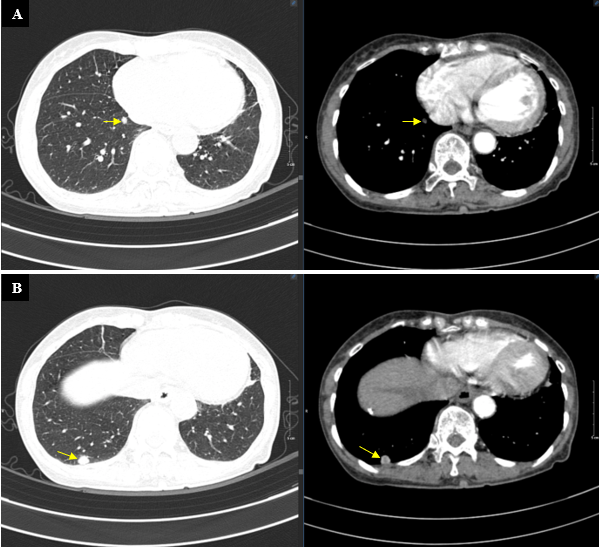

- Chụp CT lồng ngực: Nhu mô phổi hai bên rải rác vài nốt đặc, nốt lớn thuỳ trên phổi trái, kích thước 10x11mm - Theo dõi thứ phát.

Hình 3. Hình ảnh chụp CT ngực với các nốt đặc rải rác nhu mô phổi.